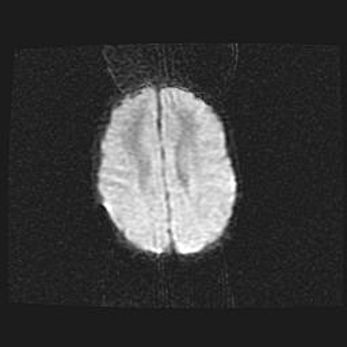

Наружная гидроцефалия с возможной атрофией височных областей.

Возраст: 28 дней

Вес: 3670 г

Пол: мужской

Окружность головы: 38 см

Срок гестации: 40 недель

Гидроцефалия головного мозга у новорожденных – это заболевание, которое характеризуется скоплением избыточного количества спинномозговой жидкости в желудочковой системе головного мозга в результате затруднения её перемещения от места выработки к месту поглощения в кровеносную систему или вследствие нарушения абсорбции. При открытой наружной форме гидроцефалии у новорожденных расширяются и переполняются субарахноидные пространства.

При нормотензивных  формах,  которые,  как  правило,  являются  следствием  перенесенных ишемических  повреждений  паренхимы  мозга,  возможно  сочетание микроцефалии  с нормотензивной гидроцефалией. В основе данных изменений лежит атрофия больших полушарий с преимущественной  локализацией  в  лобно-височных  областях.